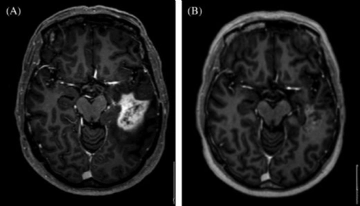

• Görüntüleme testleri (BT, MR, PET taramaları)

Beyin Metastazı Belirtileri ve Tedavisi